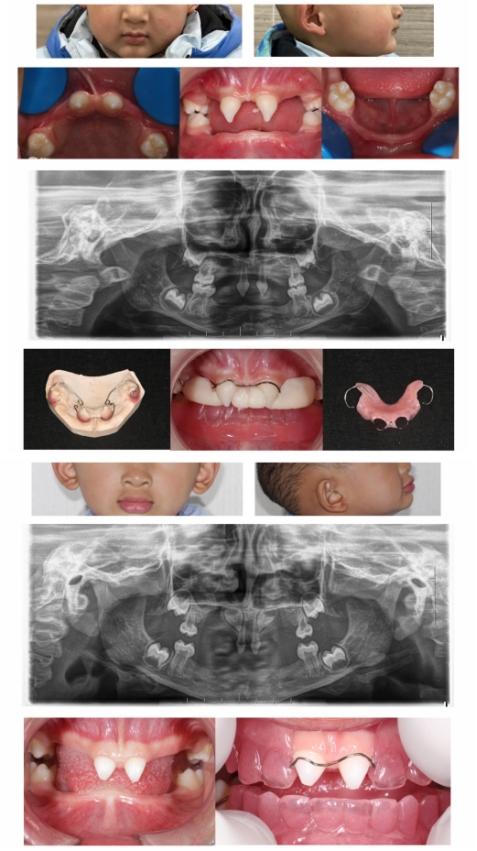

ED儿童早期修复治疗可以尽早改善发音、提高咀嚼效能,从而促进其颌骨及颜面部发育,利于美观和心理健康。修复最佳时机为四岁以上,患儿可自主配合口腔修复治疗,并且有自主佩戴义齿的能力,修复后能配合发音及咀嚼练习,家长能督促与指导。

由于低龄患儿牙弓较小,牙槽嵴条件较差,因此区别于常规义齿修复,需针对不同患儿,选用减数减径排牙、个性化自凝雕刻排牙、个性化热凝雕刻排牙等方式改良修复。